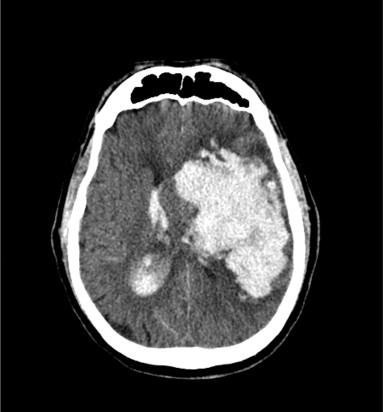

La tomografía computarizada de la cabeza es muy sensible y específica para la hemorragia intracraneal y para determinar la ubicación del sangrado.

La hemorragia intracraneal suele descubrirse al realizar una tomografía computarizada encefálica durante la valoración inmediata de una enfermedad cerebrovascular.

La sangre puede penetrar en el sistema ventricular, lo que aumenta considerablemente la morbilidad y puede provocar hidrocefalia.